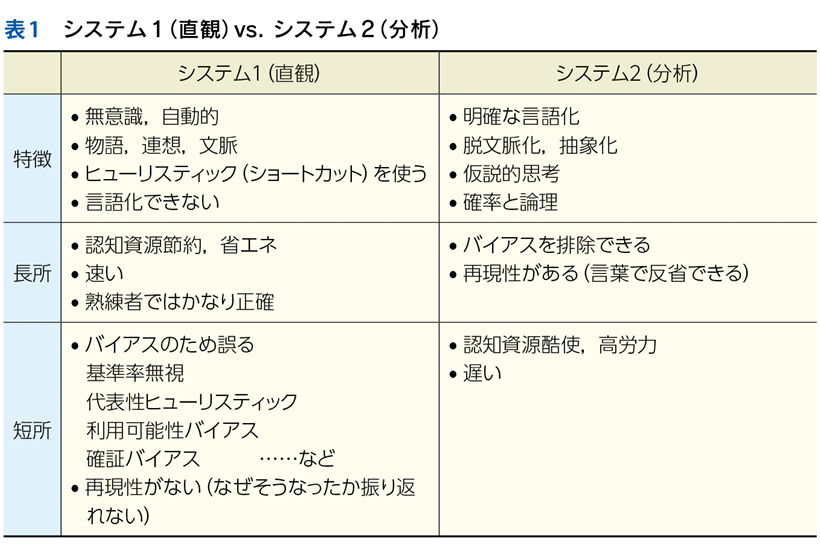

▶ システム1が使用される,短時間でのパターン認識による診断をここでは「直観的診断」,システム2に基づき,確率と論理で行われる診断を「分析的診断」と呼ぶ。

▶ semanticは直訳すれば「意味の」となるが,semantic qualifierを診断推論の文脈で訳すなら,「意味を限定する修飾語句」とでもなるだろう。先述のように,フレーミングに用いる問題を定義するにあたっては,個別具体的な情報は捨象され,抽象化・一般化された概念となっている必要がある。ゆえにSQも抽象的・一般的な医学用語に「翻訳」して表現する(表1)。

▶ システム1は確率計算をせず,「1か0か」の判断を瞬時に下す。印象的な患者背景があると,それを足掛かりにして「物語」の作成が始まり,その患者背景に疫学的に関連する疾患が決定的であるかのように直観してしまう(代表性バイアス+基準率無視)ので,診断の早期閉鎖につながる。

▶ システム2による分析的診断では,背景情報はあくまで基準率を規定するもの(可能な診断をすべて含むフレームの中で,各疾患の背景確率を提供するもの)であることを忘れず,患者背景に基づいてフレームを狭くしすぎることは避けなくてはならない。